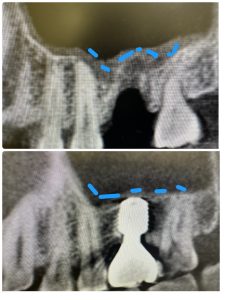

前歯オペから2ヶ月チョイで本日セット

リムーブし即再埋入、軟組織ボリューミーアップ

セメント固定からスクリュー固定変更